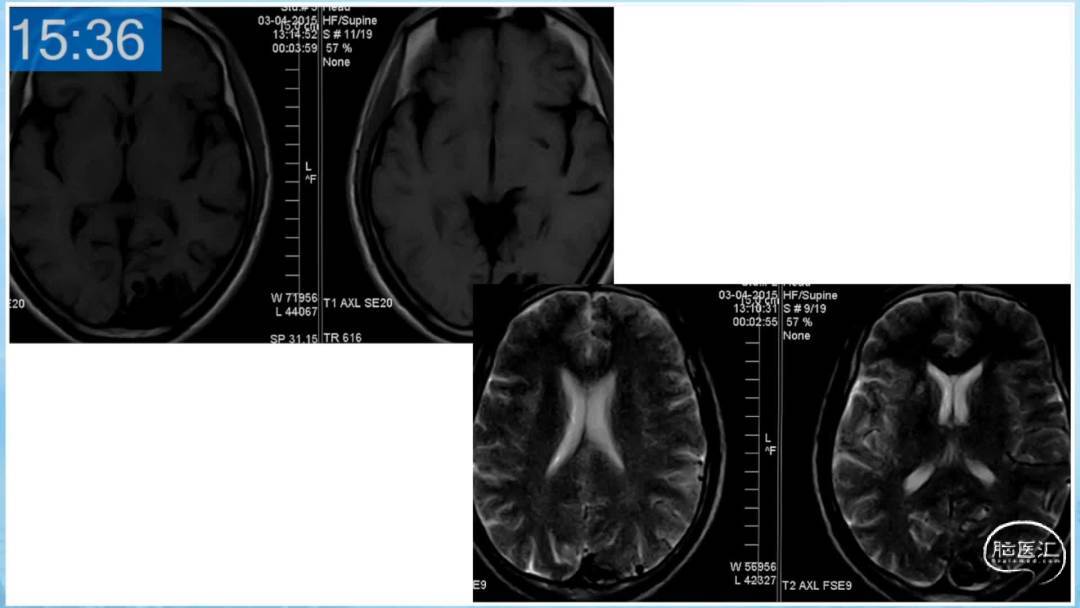

本期为大家特别分享:空军军医大学唐都医院邓剑平教授的精彩会议内容《颅内动静脉畸形的复合手术治疗》,欢迎大家阅读和分享!